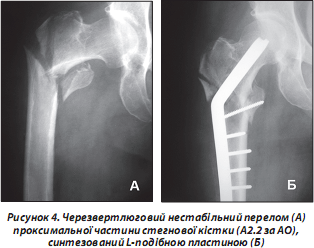

Функцію фіксатора переломів вертелюгової ділянки виконує L-подібна пластина, хоча не всі автори позитивно ставляться до її використання (рис. 4). Це пов’язано з конструктивними особливостями та неможливістю досягти динамічної міжфрагментарної компресії протягом усього терміну консолідації. Але при стабільних переломах використання пластини залишається методом вибору. Методика введення фіксатора потребує особливої ретельності від хірурга. Це стосується випадків, коли планується проводити остеосинтез переломів у людей літного віку на фоні порушення кісткової структури внаслідок остеопорозу. Введення фіксатора без дотримання методики може спричинити ще більше руйнування ділянки перелому і, як наслідок, вторинне зміщення і неможливість стабілізації фрагментів.